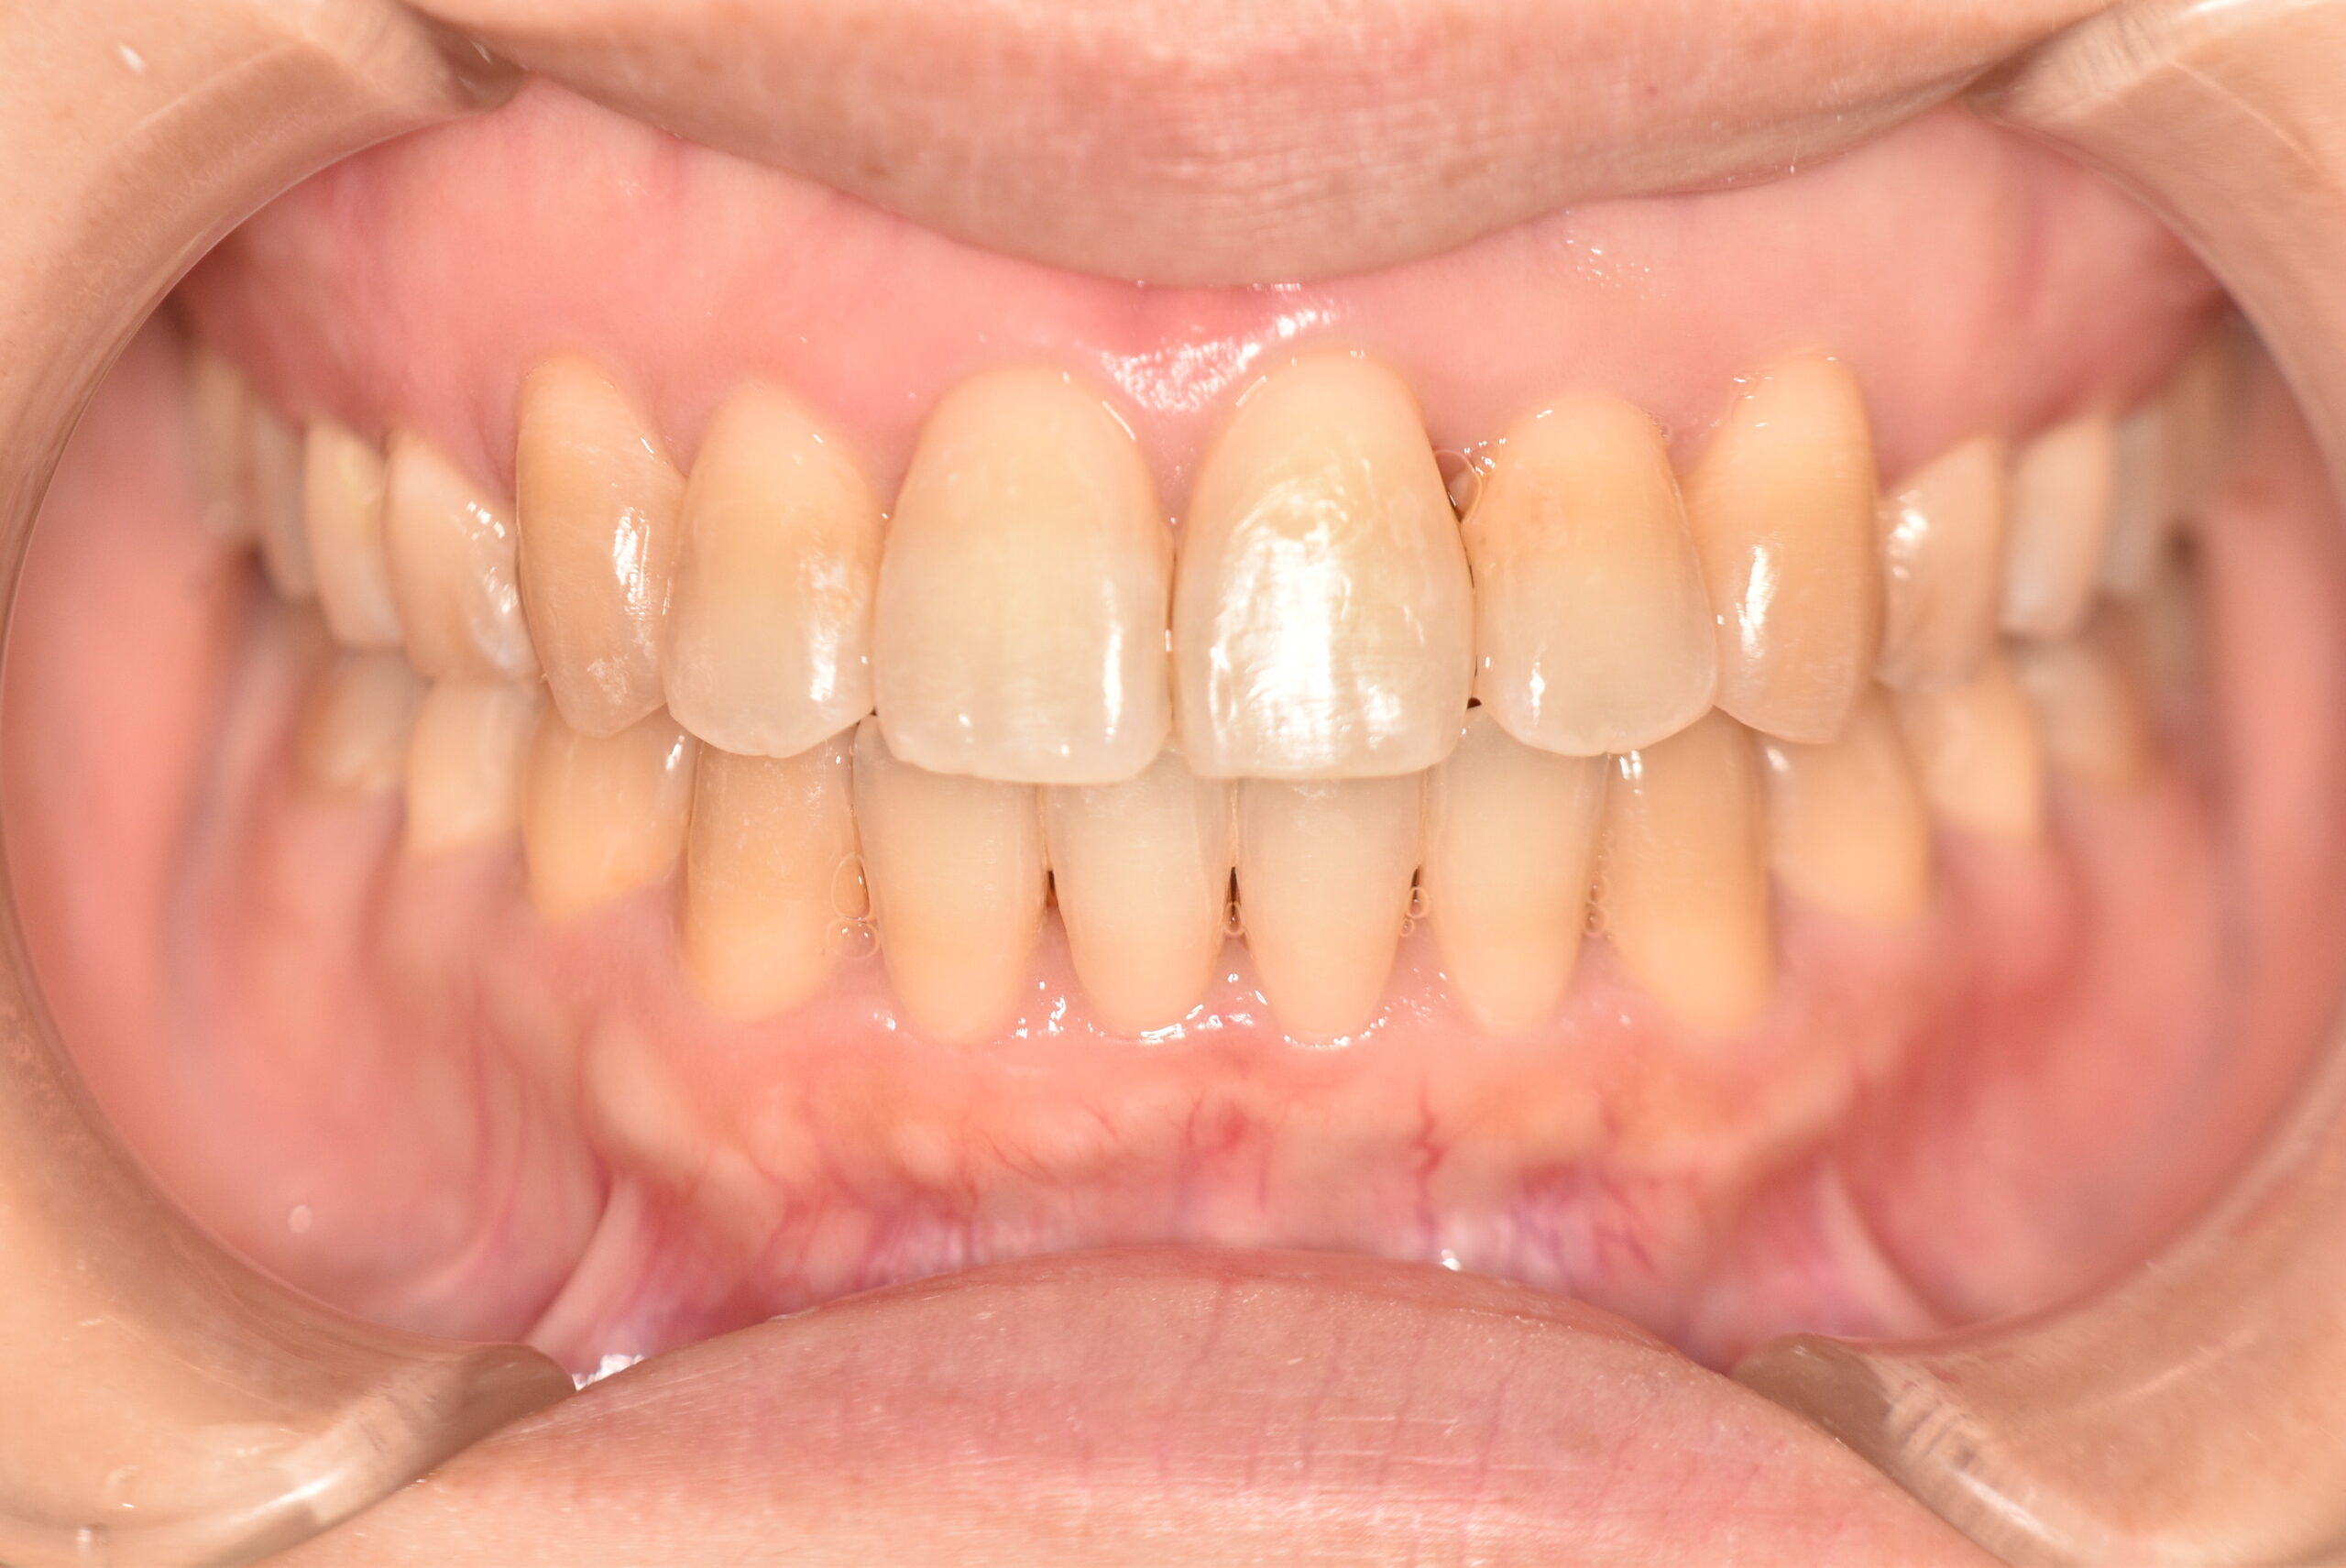

叢生(非抜歯)[2590]

初診時

年齢

31歳10ヶ月 性 別 女性

治療期間 2年7ヶ月 費 用 矯正施術料:1,000,000円 調整料:4,000円/月

治療内容の詳細 初診時31歳の女性で、前歯が奥側にあることを気にされ来院されました。

検査の結果、上下顎叢生を伴うアングルⅠ級不正咬合と診断しました。

治療としては、上顎臼歯部の遠心移動を行い、歯を配列するためのスペースを確保し、非抜歯の上、セルフライゲーションブラケット装置(デーモンシステム)で歯の配列と咬合関係の改善をを行いました。

治療期間は、2年7ヶ月でした。